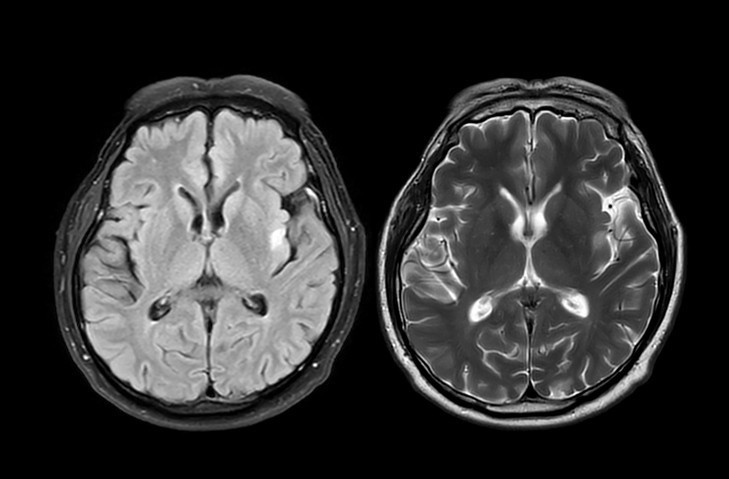

Burada amaç, vücudu ketozis denen metabolik duruma sokmak. Bu durumda vücut enerji için glukoz yerine yağdan üretilen ketonları kullanmaya başlıyor. Alzheimer hastalığında beynin enerji kullanımında ciddi bir sorun yaşanıyor.

Sağlıklı bir beyinde temel enerji kaynağı glukozdur. Ancak Alzheimer hastalığında beynin glukozu kullanma kapasitesi azalır. Nöronlar adeta aç kalır. Bu noktada keton cisimcikleri, beyin için alternatif ve daha kolay kullanılabilen bir yakıt haline geliyor.

Araştırmalara göre ketojenik diyet Alzheimer hastalarında tedaviye olumlu etki ediyor. Ketojenik diyet karbonhidratı ciddi biçimde kısıtlayıp yağdan zengin bir beslenme modeli sunarak vücudu keton üretimine yönlendiriyor. Böylece beyin, glukoz yerine ketonları enerji kaynağı olarak kullanabiliyor. Yani beynin aç kalan hücrelerine alternatif bir enerji kapısı açılıyor.